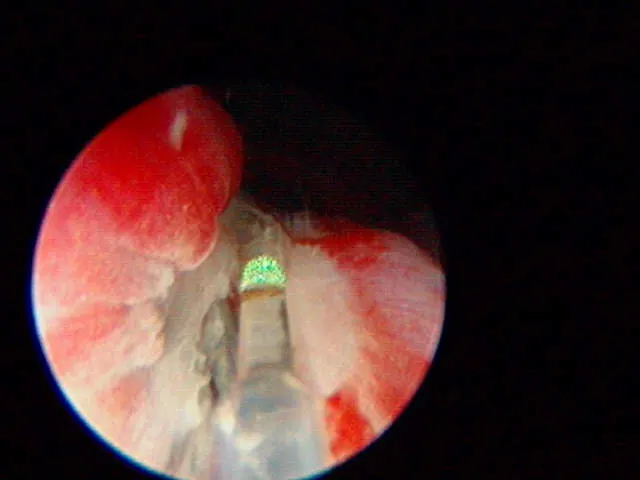

A diode laser or radiofrequency is used to longitudinally incise the ureter from the ectopic ureteral orifice to the level of the trigone.

A

The plastic stent has been placed in the EU and the laser (green tip) is ablating the tissue over the stent.